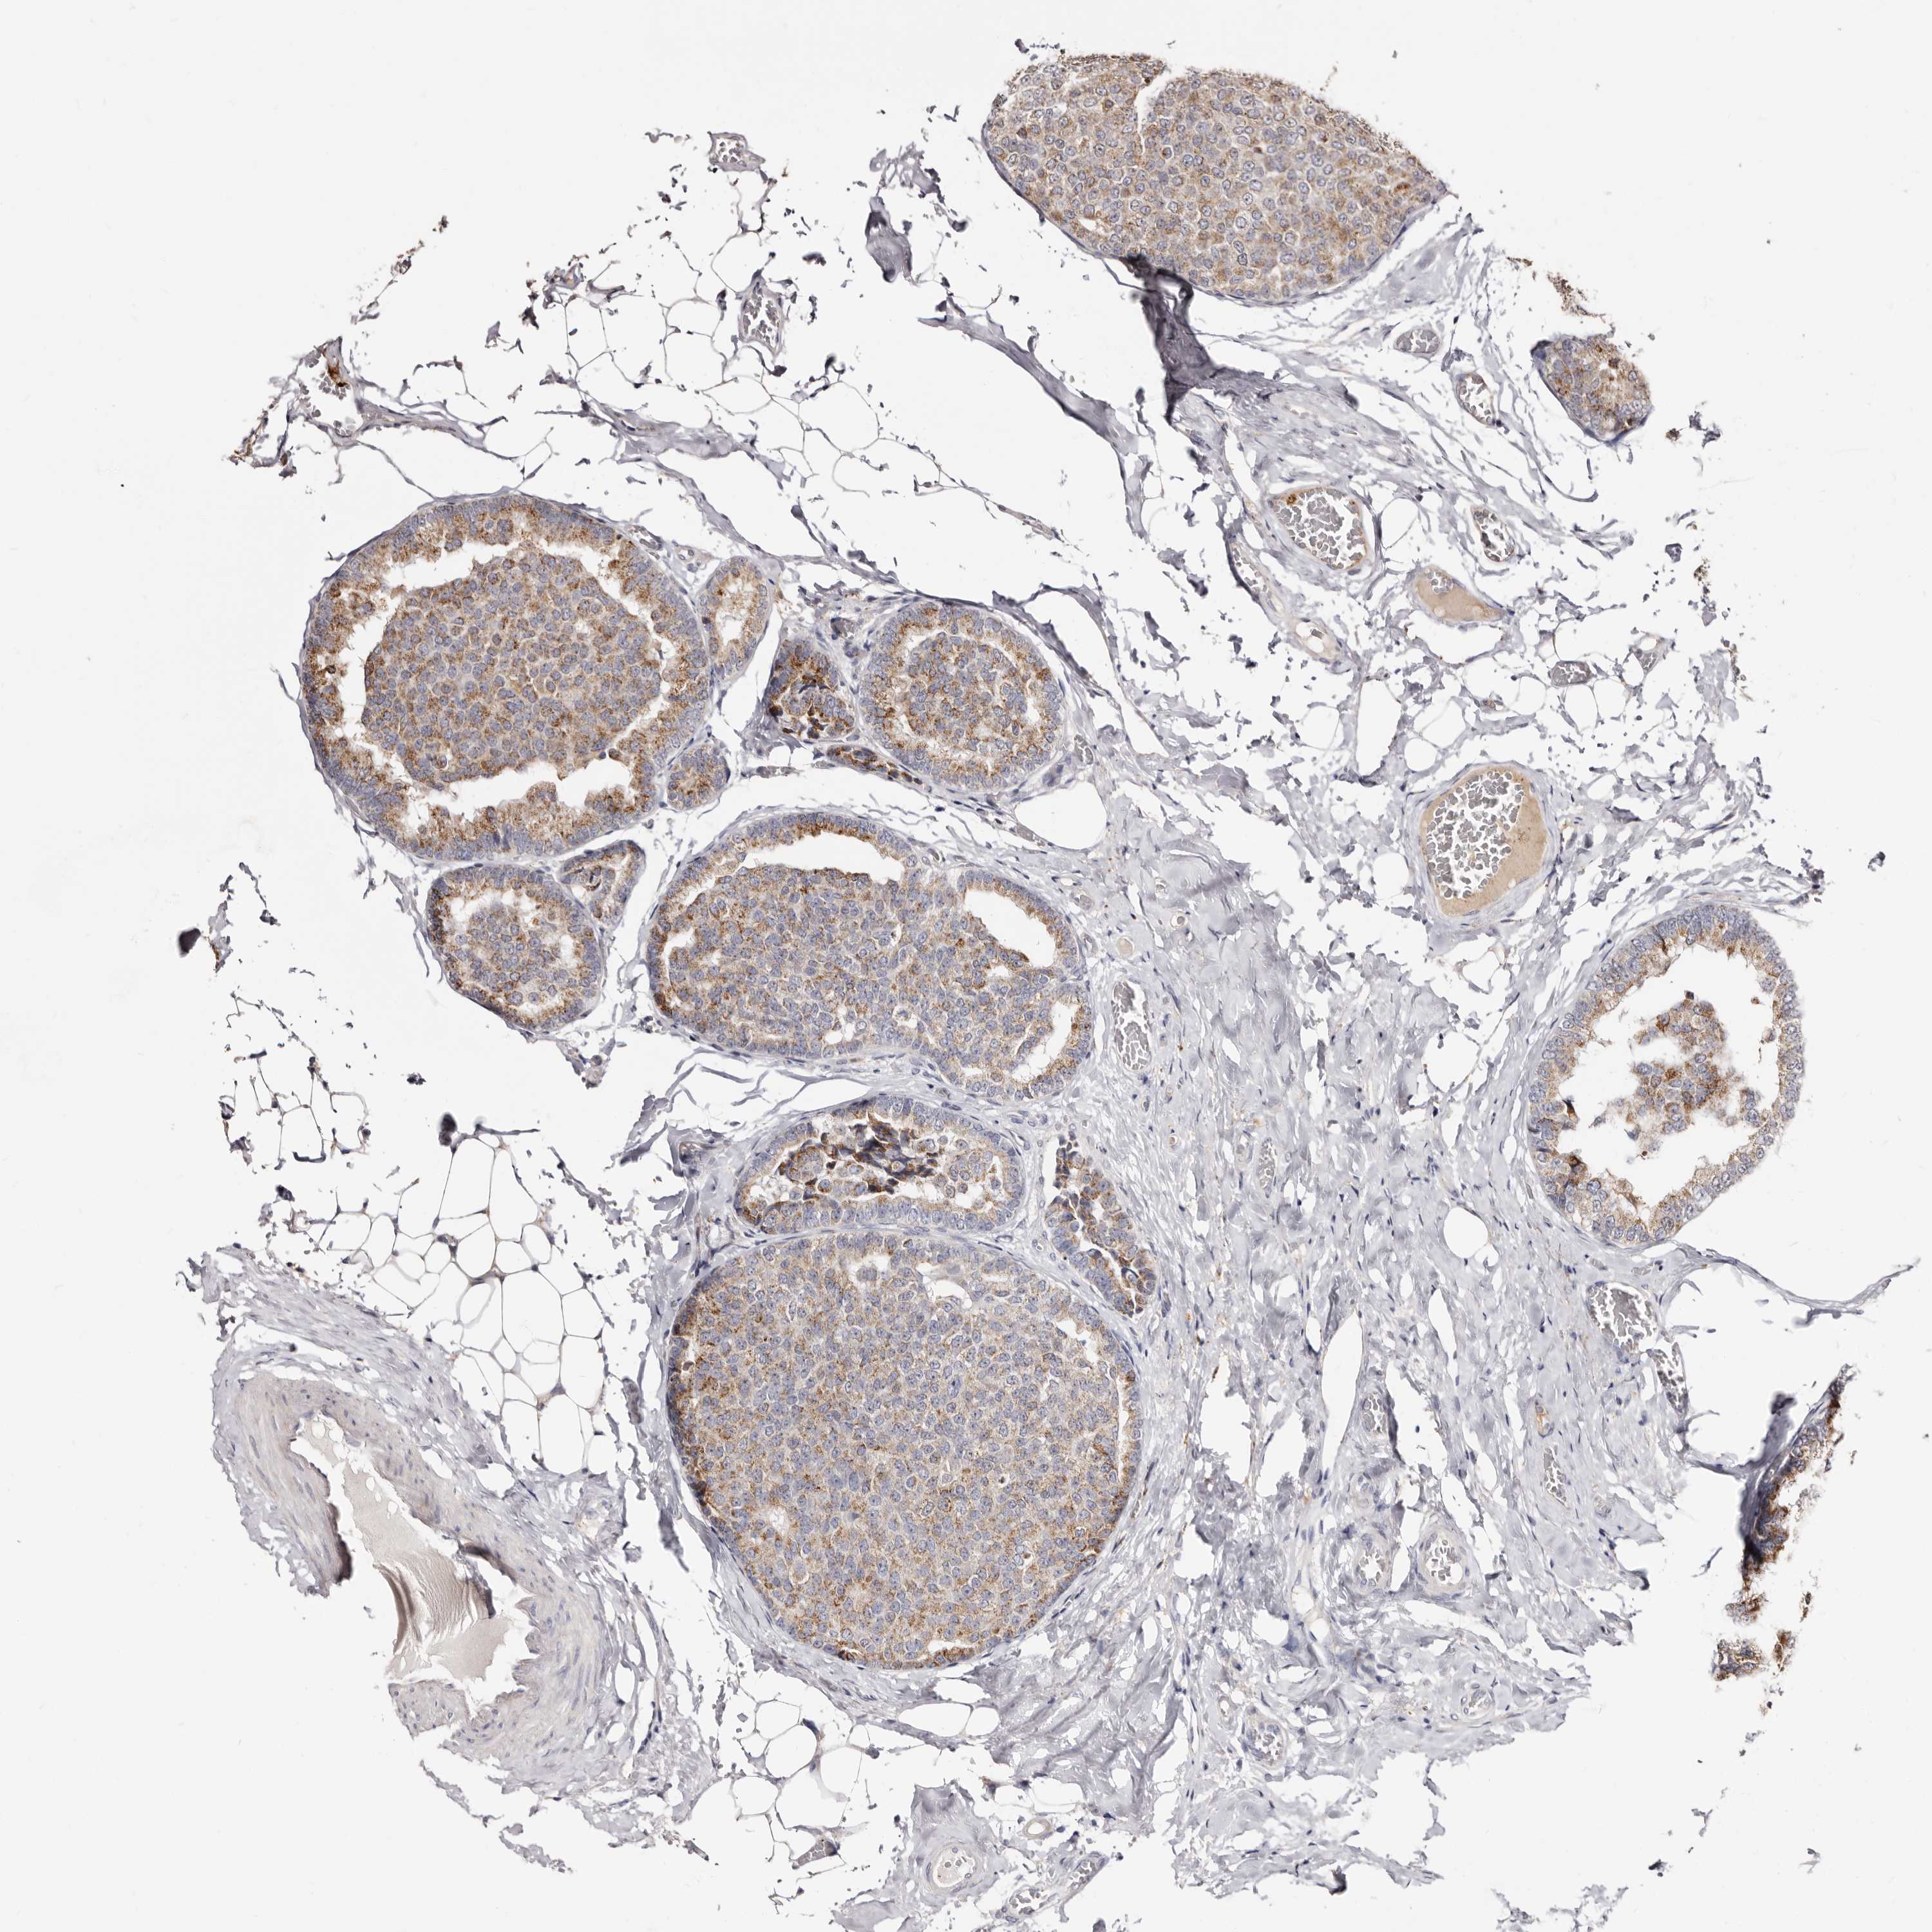

CANCER BREAST CANCER Show tissue menu

BRCA TCGA BRCA VALIDATION PROTEIN EXPRESSION